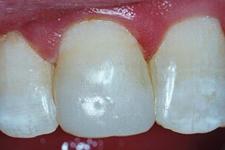

Sanatate parodontala

culoare roz coral

gingia este ferm atasata de dinte

lipsa sângerarii

aspect de "gravura punctata"